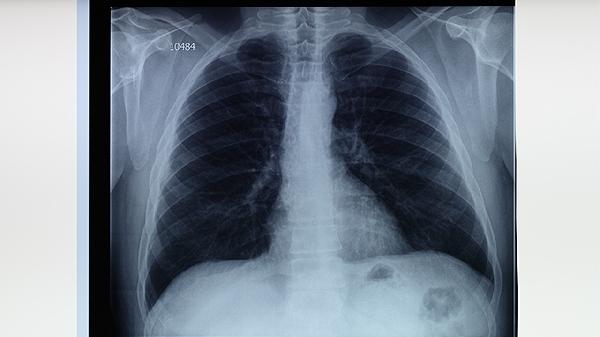

肺结核患者在治疗期间,饮食应遵循高蛋白、高维生素、易消化的原则。除了适量食用鱼类,还应保证足量的瘦肉、蛋类、奶制品及新鲜蔬菜水果的摄入。务必严格遵医嘱完成全程、规律的抗结核药物治疗,不可自行停药或更改剂量。定期复查肝肾功能、血常规及胸部影像学检查,监测病情变化和治疗反应。保持居住环境通风,注意个人卫生,适当休息,避免劳累,这些综合措施共同助力于疾病的康复。